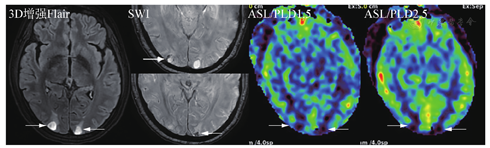

另外,DWI由于非常有诊断价值和扫描时间短,建议始终放在平扫序列里。而注射造影剂前的平扫中,只扫Flair序列,T2放在增强后扫描。优化标准中,主要增加了DSC灌注扫描(可能对鉴别肿瘤复发和放射性坏死有用)、增强后Flair(显示软脑膜转移病变较常规增强T1MRI效果好)以及增强后长时间延迟扫描(60~105 min,以期显示小病灶)。关于增强后Flair序列,对于脑膜转移的增强显示能力已被认可。对于脑实质内的转移瘤病灶,并不能增加诊断信息,但是对于靠近皮质的表浅病灶,显示能力超过常规增强T1,详见图3、图4。不同MR扫描机的序列名称不同,但序列的本质一致。

为了增加诊断信息和科研需求,可依据实际情况选择额外MRI序列,包括SWI、ASL及前面提到的增强后Flair等(图6)。笔者体会是转移瘤出血非常常见,常规MRI一些序列也可以分辨,但SWI显示更好。ASL的价值也有很多研究报道,转移瘤因瘤内成分不同而显示高、低灌注或混杂信号,在以囊性为主病灶中分辨率有限。但在鉴别转移瘤和非肿瘤病变中有价值,ASL值得推荐。但ASL扫描时间较长,且图像有变形,解读时以黑白图像评估可能更可靠。

关于软脑膜转移,常规增强T1SE序列常难以发现,GRE序列由于血管增强效应,会导致脑沟内多发的条状或者点状高信号,即高估效应,带来假脑膜转移瘤征象。近年来,增强后Flair序列在显示脑膜转移瘤方面显示出一定优势,尤其在一定时间的延迟后,更可以确认脑膜转移的有无,从而准确评估预后和制定治疗决策。